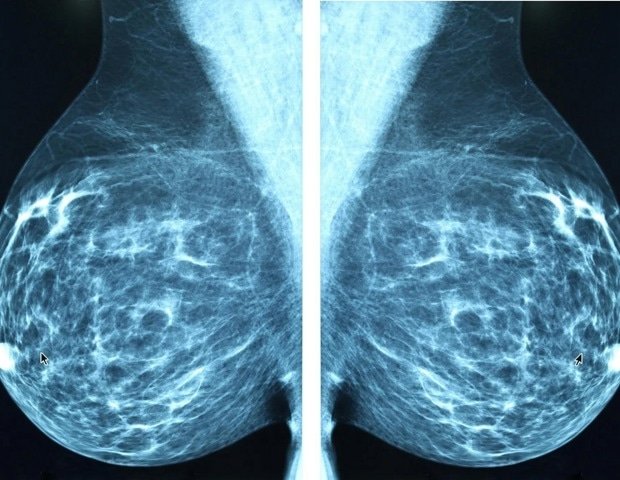

The Alberta Adolescent and Young Adult Cancer Survivor Study includes all people in Alberta aged 15 to 39 who were diagnosed with a first cancer between 1983 and 2017. During this 34-year study period, researchers analyzed future cancer risk to better understand the impact on this demographic and the risk of future disease and death. Of 24,459 people with a median follow-up of 7.4 years, 1,442 (6%) developed at least one subsequent cancer. The most common types of cancer were lymphoma and breast cancer, followed by cancer. Breast, colorectal, and lung cancers were the most common new cancers, accounting for 43% of subsequent primary neoplasms.

“While people with nearly all types of adolescent and young adult cancers studied were at increased risk of developing subsequent primary neoplasms, Hodgkin lymphoma and breast cancer survivors were identified as a particularly vulnerable population, with nearly one-third of subsequent primary neoplasms occurring after diagnosis in these survivor groups at 5 years survival,” the authors write. “These findings are consistent with previous studies and reflect the well-established late effects of radiotherapy, chemotherapy, and hormone therapy.”

Thirty years after initial diagnosis, one in six adolescent and young adult cancer survivors will experience a new cancer. Because these cancers develop decades earlier in survivors than in the general population, the authors suggest that early screening may be beneficial.

”Our findings suggest that early cancer surveillance in this population may be warranted, which is consistent with many survivorship guidelines that recommend early breast and colorectal cancer surveillance for at-risk cancer survivors.” writes the author.